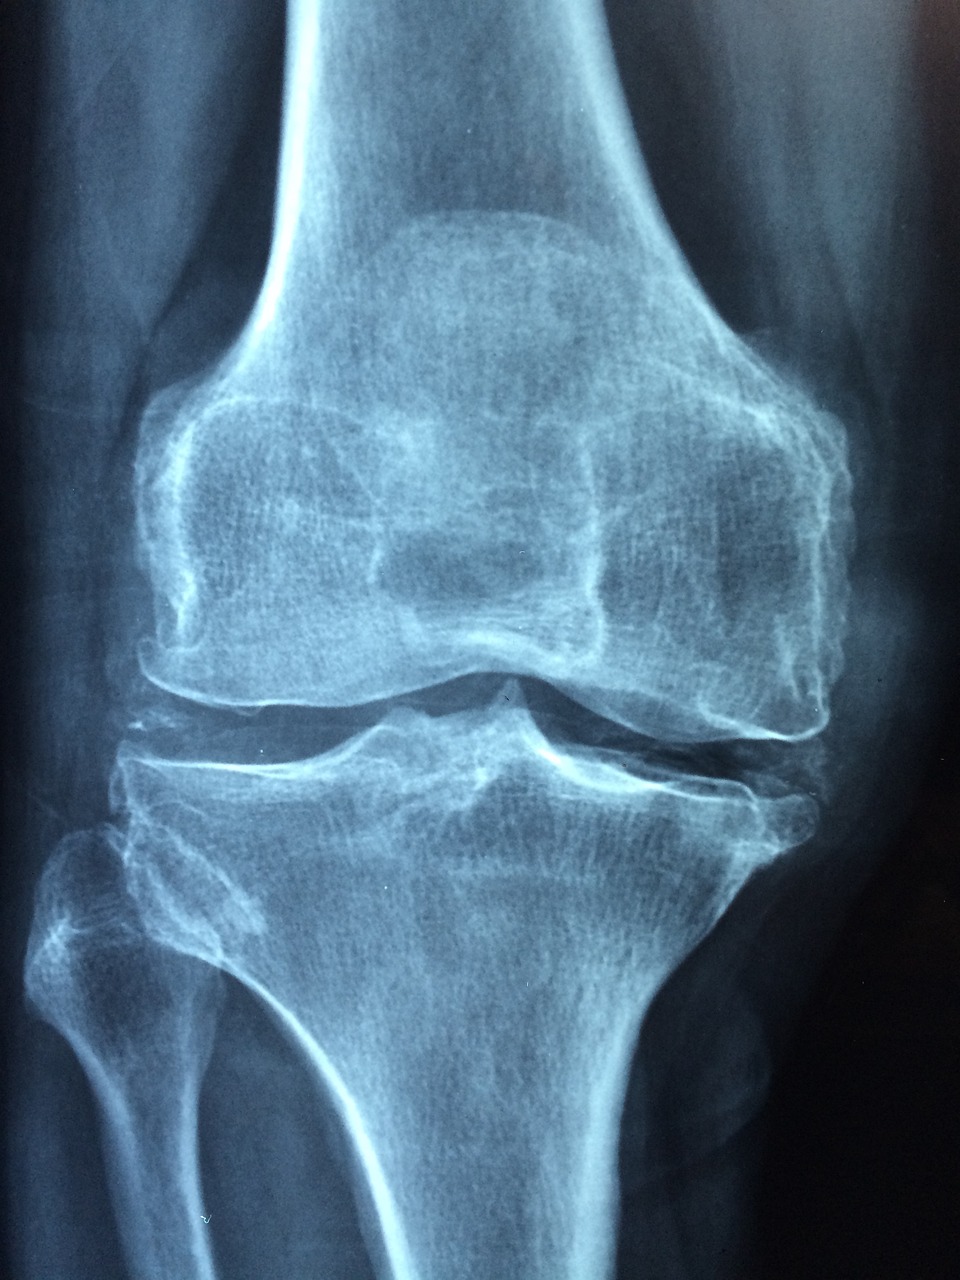

3️⃣ 수술 후 염증이 생겼을 때 나타나는 대표 증상들

✅ 무릎 인공관절 수술 후 염증이 실제로 발생하면, 단순한 불편함을 넘어 뚜렷하고 불쾌한 변화가 동반됩니다.

이때는 몸이 스스로 위험 신호를 보내고 있는 것이라 볼 수 있습니다.

● 수술 부위의 강한 통증과 지속적인 부기

처음보다 더 심한 통증, 붓기가 계속되고 있다면 염증일 가능성이 큽니다.

이 통증은 앉거나 누워 있어도 사라지지 않으며, 움직이면 더욱 심해집니다.

● 수술 부위 피부가 붉게 변하고 열이 난다

피부 표면이 ‘뜨겁고 딱딱해지며’ 손으로 만졌을 때 화끈거리는 열감이 느껴질 수 있습니다.

● 무릎이 굽혀지지 않거나 관절이 굳는 느낌

염증이 관절 내부로 퍼질 경우, 재활운동도 어려워지고 관절 유착이 생길 수 있습니다.

● 몸살 기운, 식욕 저하, 피로감 동반

전신에 영향을 줄 정도의 염증일 경우, 몸 전체가 축 처지고 기력이 떨어지는 현상이 나타납니다.

💡 만약 진물이 계속 흐르거나, 하루가 다르게 상태가 나빠지고 있다면

즉시 병원을 찾아야 하며 항생제 치료나 재수술이 필요할 수도 있습니다.

절대 시간을 끌지 마세요.